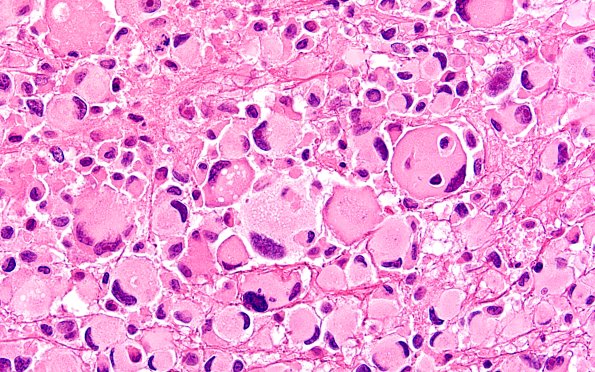

Pleomorphic Xanthoastrocytoma (PXA)

22B17 PXA (Case 22) H&E B2 60X 12

Additional examples of possible emperipolesis? (H&E)